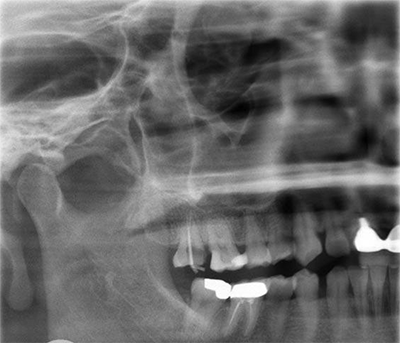

术前X-ray

术前X-ray局部放大图